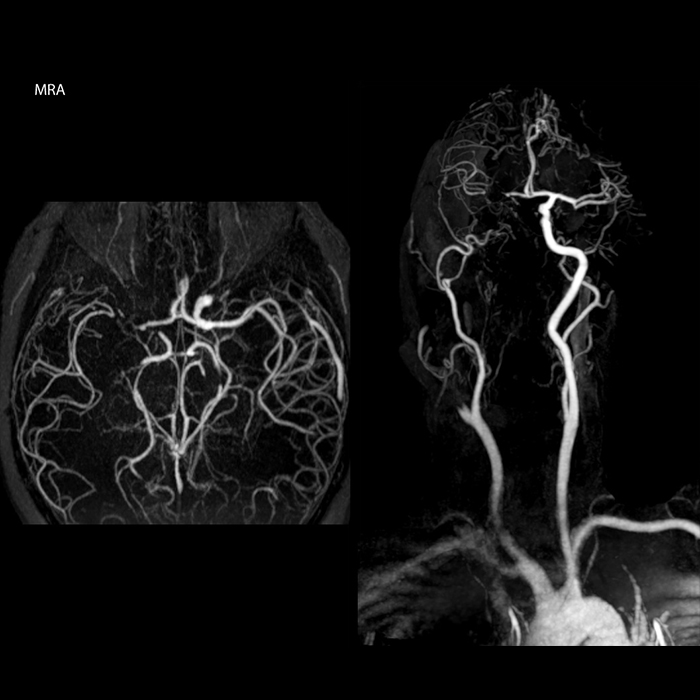

“Ingenia provides great flexibility in the parameters setting. We can tune a sequence the way we want,” says Dr. Savatovsky. “For example, in a stroke exam we use a FLAIR sequence of about two minutes instead of the four-minute FLAIR we use for MS. The diffusion is 30 seconds, the T2*-weighted scan is 30 seconds, the angiography scan time is less than one minute. Ingenia is a great scanner in that situation; even with these fast sequences we can achieve good images with good SNR. When the first sequence tells us that it’s not an ischemic stroke but a hemorrhagic stroke, we may switch to a time-resolved angiography to look for vascular malformations and venous thrombosis.

“Every center is different, but for me the ideal protocol for stroke includes diffusion weighted imaging, FLAIR, and fast susceptibility imaging,” says Dr. Savatovsky. “Our fast susceptibility weighted imaging takes 50 seconds, so it’s as fast as T2*-weighted imaging. It visualizes hemorrhage but also the clots. We also do 3D MR angiography that provides information on cervical and brain vessels. If the patient does not need immediate treatment, or if additional information is needed to decide on treatment, we might also add perfusion imaging and post-contrast T1-weighted imaging.”